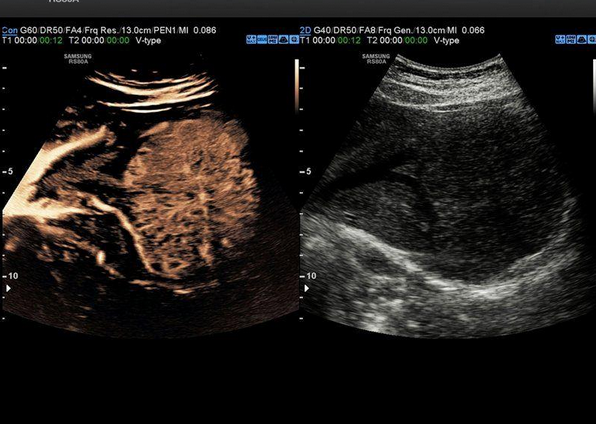

1. ფოტო -ღვიძლი CEUS+ (კონტრასტული ულტრაბგერითი) და VesselMax (სისხლძარღვთა გაძლიერებული ვიზუალიზაცია) რეჟიმში.